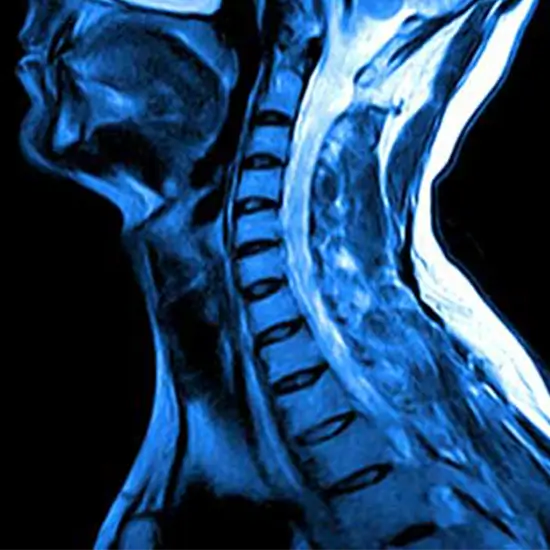

MRI cervical lumbar spine is an imaging technique that obtains high-resolution images of the cervical spine (vertebrae in the back of the neck) and lumbar spine (bones, disks, spinal cord, and other structures in the lower back).

An MRI Cervical lumbar spine is ordered to detect a variety of conditions in the lower back, the neck, and upper back area.